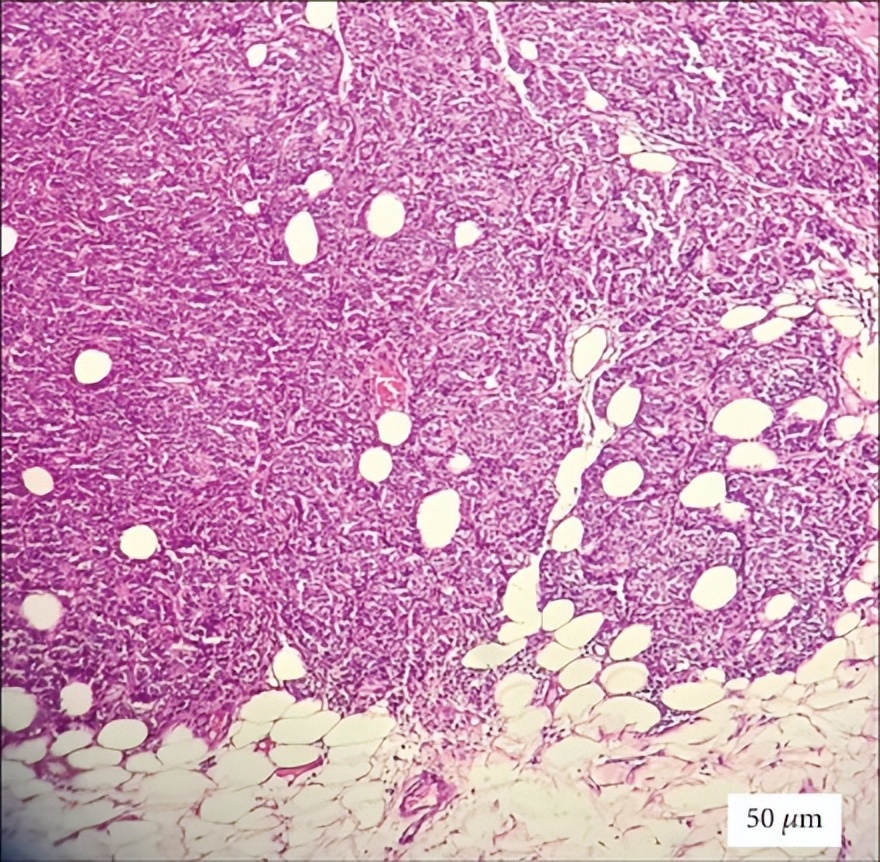

外阴病变活检证实为浸润性导管乳腺癌转移:组织病理学检查显示非典型上皮细胞呈实性增殖,符合转移性乳腺癌特征。肿瘤细胞排列成实性片状,而非单细胞条索状。免疫组织化学分析显示雌激素受体表达阳性,孕激素受体表达阴性,且无HER2蛋白过表达(评分1+)(图1)。

图1:外阴病变组织病理学检查(H&E染色,20倍放大)显示非典型上皮细胞呈实性增殖,符合转移性乳腺癌。比例尺=50μm。